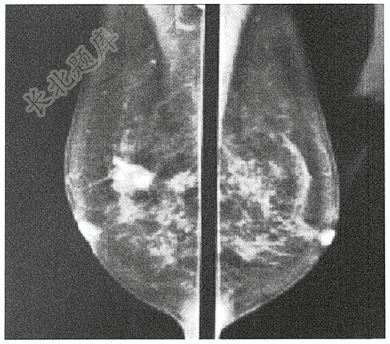

- 单项选择题老年女性,55岁,因发现右乳肿物周入院。患者右乳外上象限可见2×3cm肿物,质硬,固定,局部皮肤可见皱缩,行钼钯如下图,最有可能的诊断是( )

A、乳腺纤维瘤

B、乳腺癌

C、乳腺囊性症状

D、乳腺腺病

E、乳腺炎